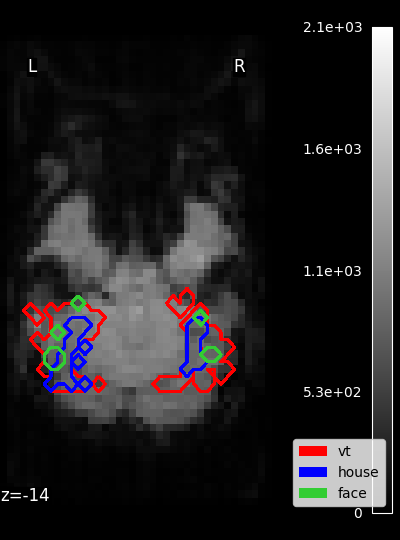

../_images/sphx_glr_plot_haxby_masks_001.png

Masks